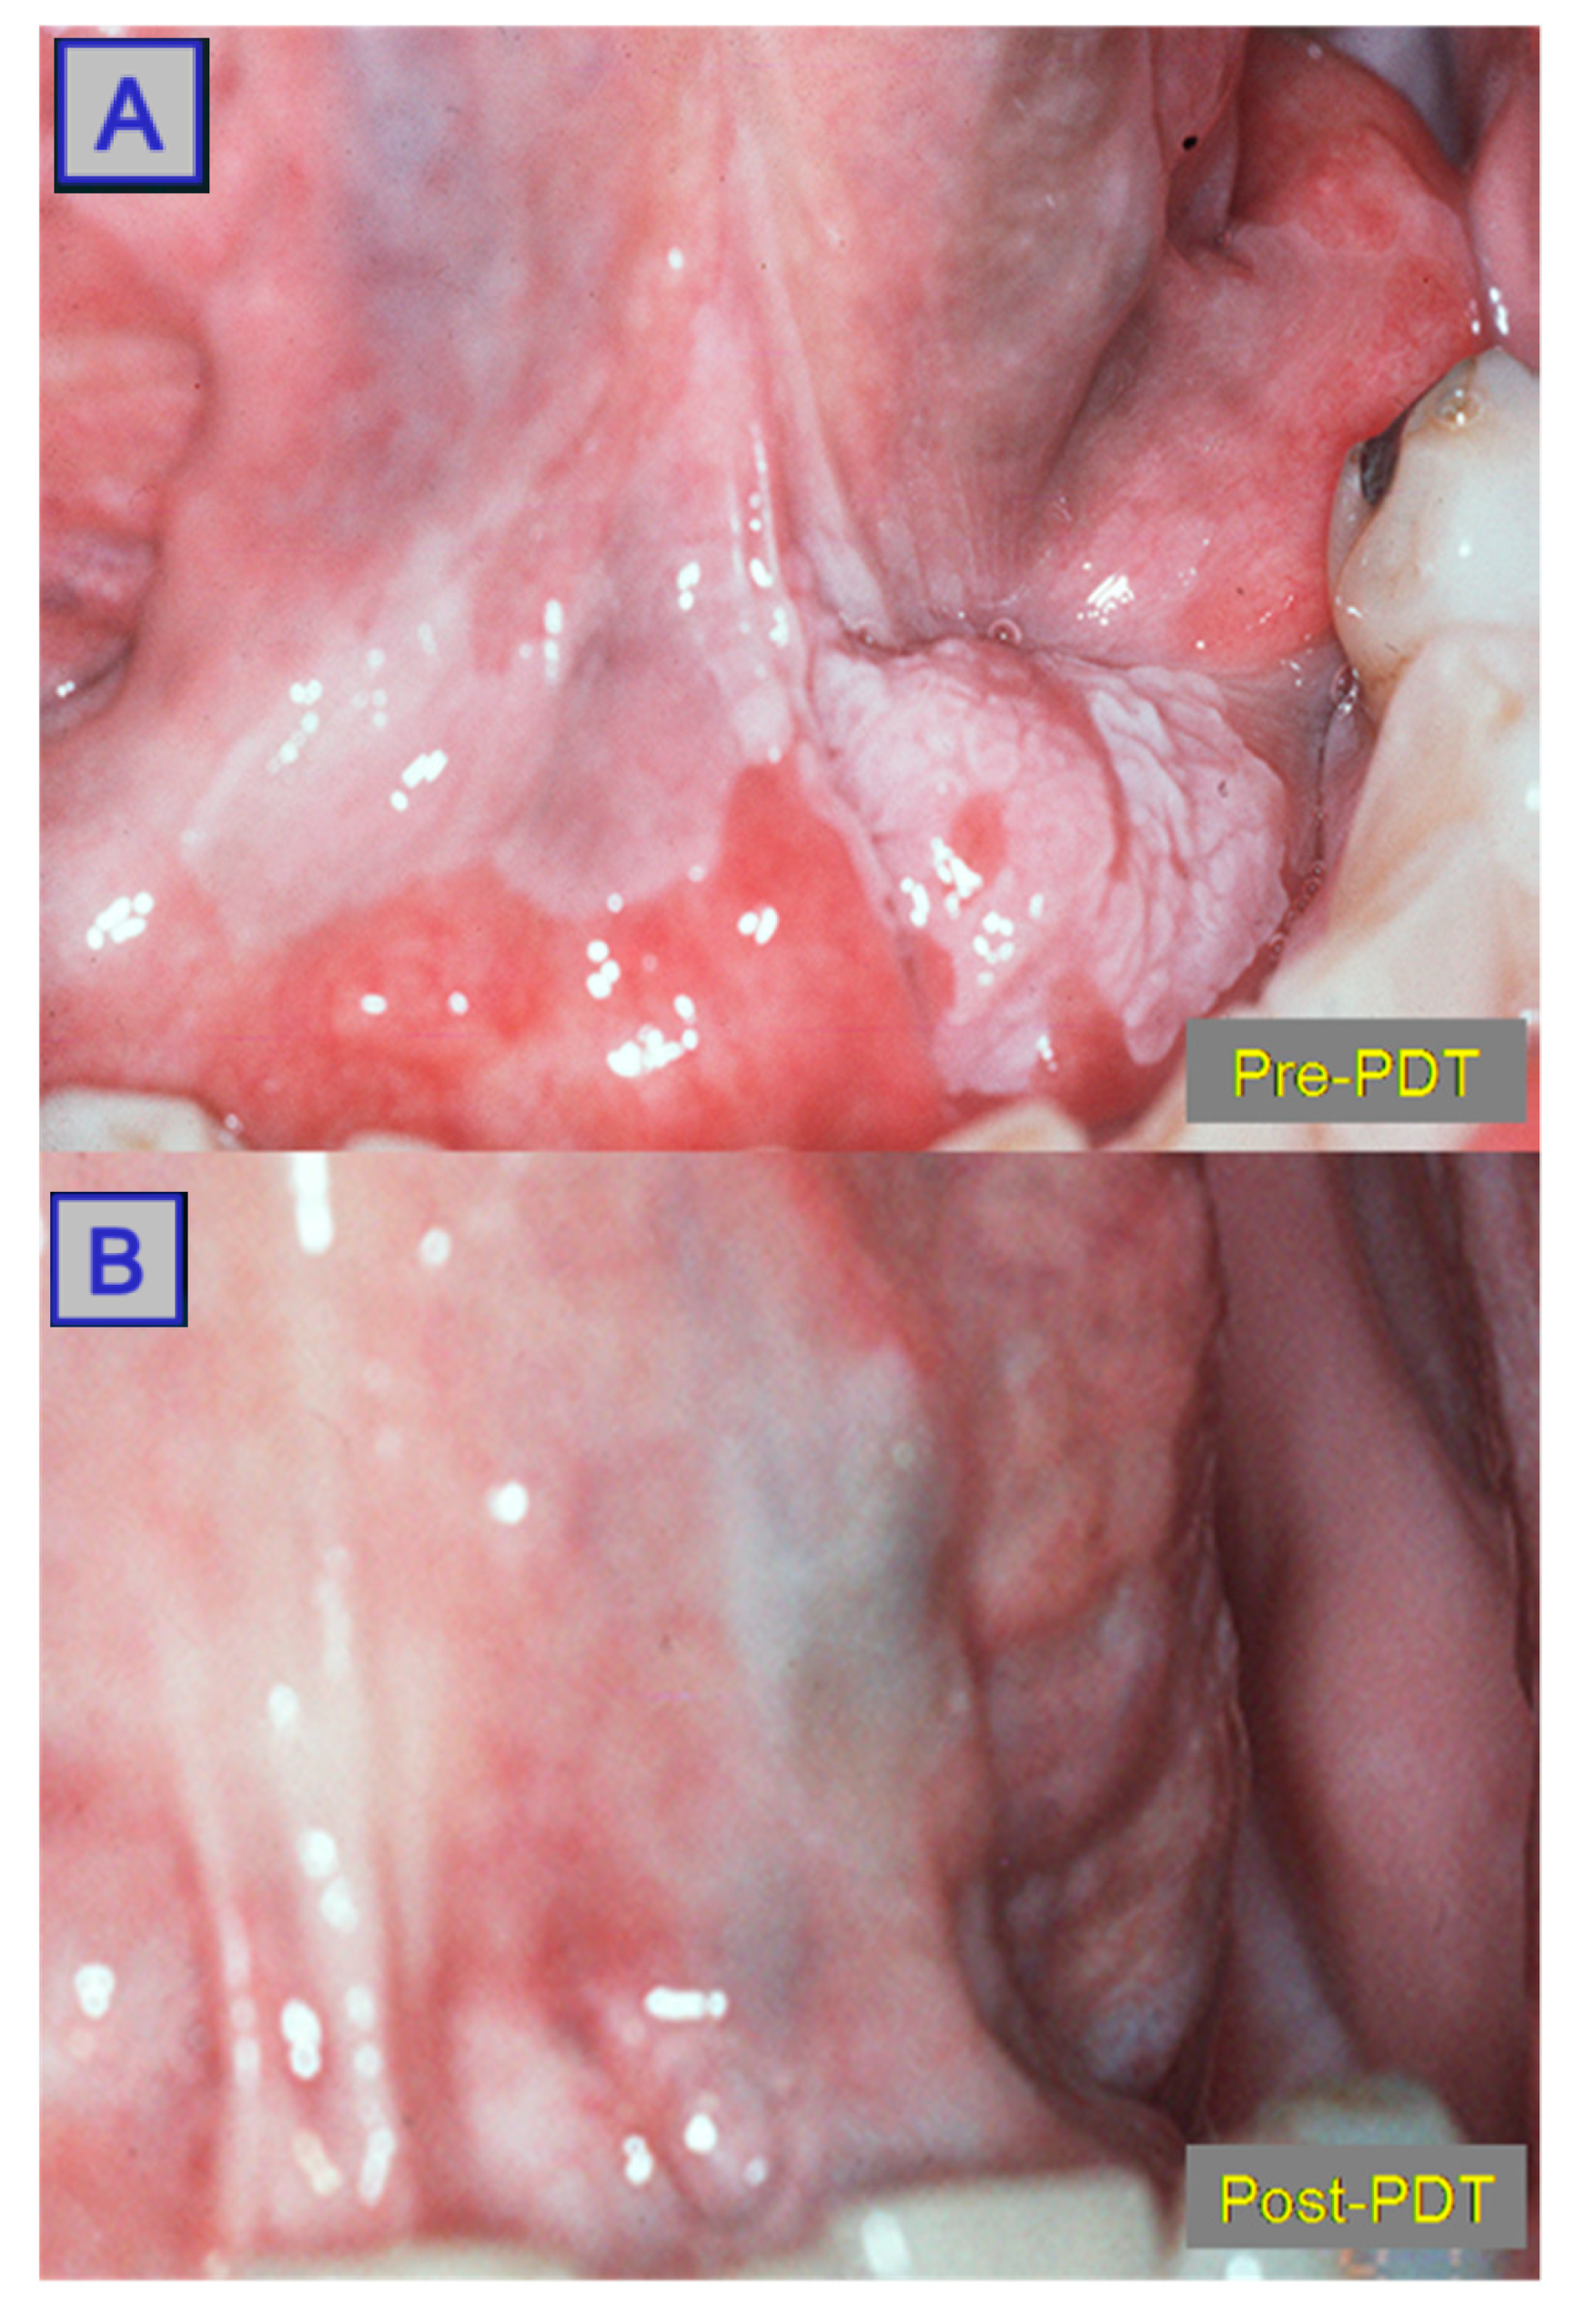

- Hamdoon, Z.; Jerjes, W.; Upile, T.; Akram, S.; Hopper, C. Metastatic renal cell carcinoma to the orofacial region: A novel method to alleviate symptoms and control disease progression. Photodiagn. Photodyn. Ther. 2010, 7, 246–250. [Google Scholar] [CrossRef]